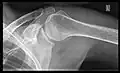

In the UK, the standard projections of the shoulder are AP and Lateral Scapula or Axillary Projection.[15]

-

Transaxillary -

Y-projection